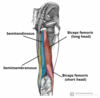

What is this muscle?

What is this muscle?

Latissimus Dorsi